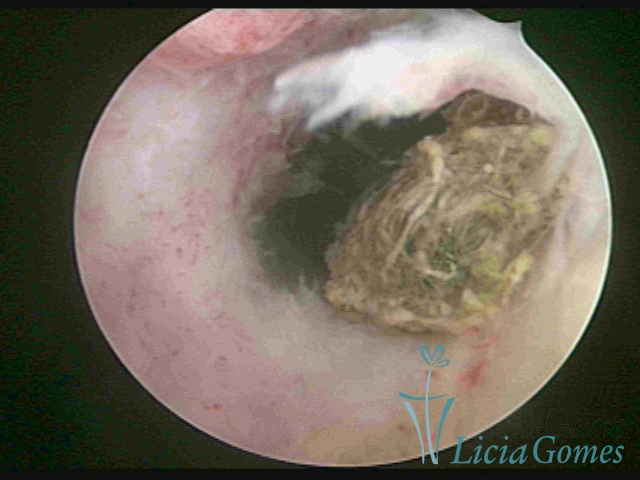

Uterine cavity with a fragmented IUD debris, inserted 46 years ago.

×